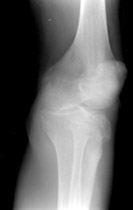

• Also known as "fender" or "bumper" fractures, tibial plateau fractures most often are the result of a moving vehicle striking the knee.

• Plateau fractures (medial and lateral) are the most common fracture sustained at the proximal tibia.

• When depression is not present, fracture may be difficult to recognize with standard radiographic exam. Alternative views and/or CT may be required for diagnosis.

• Associated damage to the anterior cruciate ligament, medial collateral ligament and medial meniscus is common due to valgus stress placed on the knee during injury.

• Postraumatic arthritis and malunion can result.